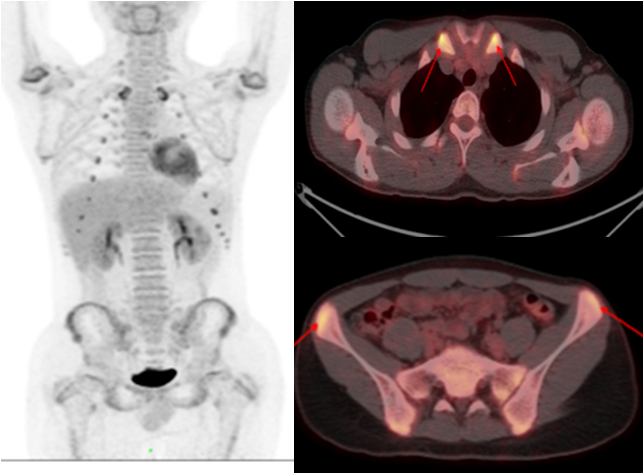

老年男性,反復發(fā)熱1年余;10年前因主動脈夾層行支架植入。PET/CT顯示支架周圍主動脈管壁增厚,代謝明顯增高,診斷為支架周圍感染。

少年男性,間斷發(fā)熱半年,一直未找到原因。PET/CT 顯示多處關節(jié)、軟骨高代謝灶,最終診斷為復發(fā)性多軟骨炎導致的不明原因發(fā)熱,經(jīng)指導后臨床治療效果良好。